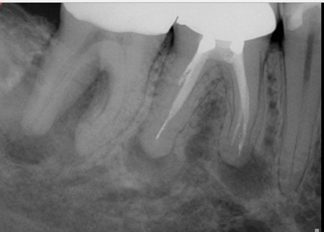

(5.) Preoperative radiograph of tooth No. 19 following a pulpectomy procedure that was complicated by an intraoperative furcal perforation.

Figure 5

(6.) Postoperative radiograph showing immediate perforation repair using MTA followed by complete obturation.

Figure 6

(7.) One-year follow-up periapical and bitewing radiographs demonstrating the absence of apical pathosis or furcal pathosis at the site of

the perforation.

Figure 7

(8.) One-year follow-up periapical and bitewing radiographs demonstrating the absence of apical pathosis or furcal pathosis at the site of

Figure 8

Bioceramic materials, including MTA, offer a predictable means to repair iatrogenic furcal and lateral root perforations (Figure 5 through Figure 8).16 Overall, studies favor the use of MTA over other nonbioceramic materials for perforation repair,17,18 which is attributable to its superior seal. In addition, its inherent biocompatibility and osteoconductivity facilitates the repair of localized hard tissue damage. The key to successful perforation repair, regardless of the material utilized, is in the immediacy of its performance and completion before bacterial cross-contamination and inflammation-mediated bone loss can occur.17